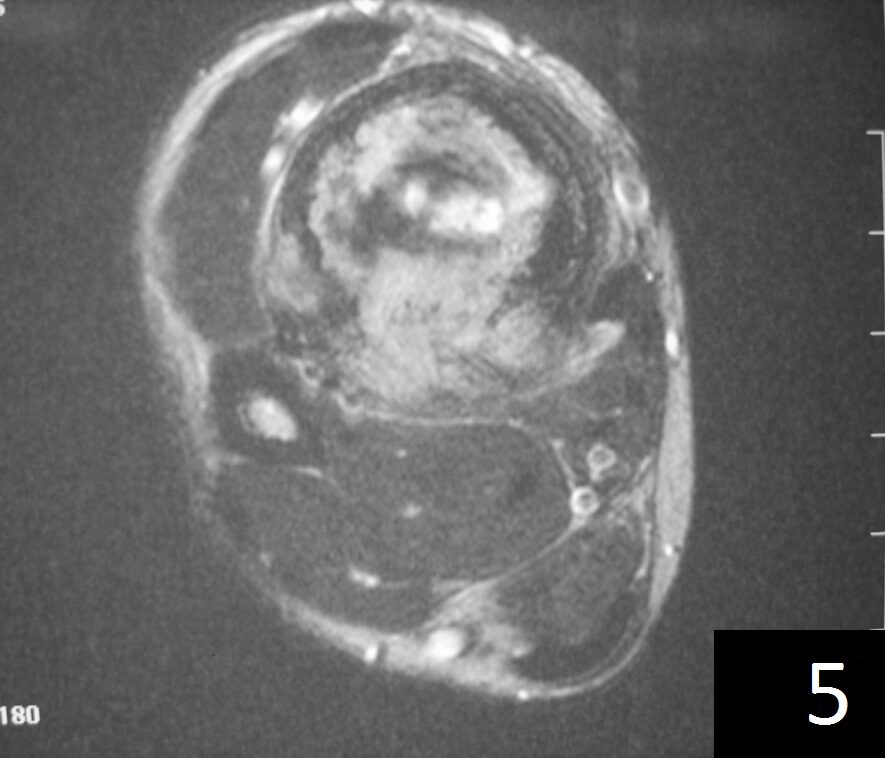

MRI (Fig. 4-5)

• Ideal to describe soft tissue involvement

• Sequences often follow that of fibrous tissue with low signal on T1 weighted and T 2 weighted images

Fig. 4-5: Axial MRI of leg demonstrates a tibia lesion with cortical destruction and soft tissue involvement.